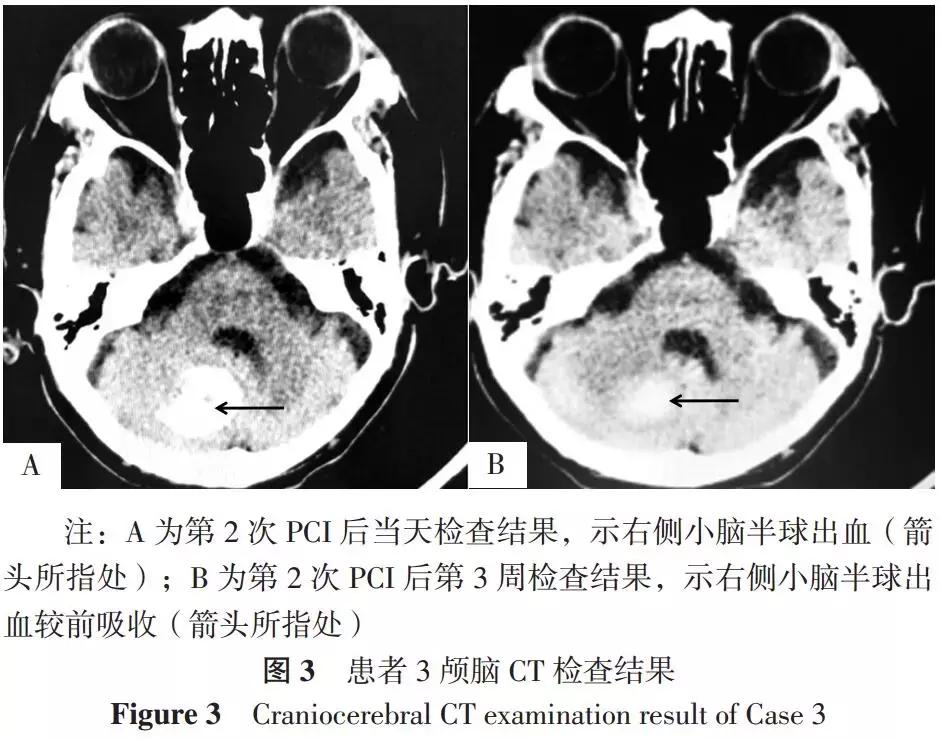

患者3,男,78岁,因“反复胸闷痛10余年,再发、加重11 h”于2018-01-02入住广东省中医院。患者既往有冠心病、高血压病史,入院后行心电图检查发现窦性心律、V2~V5导联ST段压低、不完全性右束支传导阻滞,检测cTnT为0.492 μg/L。入院诊断:急性心肌梗死、冠心病、高血压2级(很高危),遂给予阿司匹林、替格瑞洛抗血小板聚集,依诺肝素抗凝,瑞舒伐他汀调脂、稳定斑块等。后行急诊冠状动脉造影发现左主干中段斑块形成、狭窄率约为70%,前三叉开口狭窄率约为80%,左前降支完全闭塞、近段病变局部可见钙化影,左回旋支开口及近段狭窄率约为60%、中段次全闭塞(狭窄率约为99%)、远段近端狭窄率约为70%,第一对角支弥漫性斑块形成,右冠状动脉多发狭窄、近段狭窄率约为80%、中段狭窄率约为90%,后三叉开口狭窄率约为75%、远端可见至左前降支中段侧支循环形成,遂于左回旋支中段植入2.50 mm×38.00 mm支架1枚,于右冠状动脉中远段狭窄处至开口依次植入2.75 mm×38.00 mm、3.00 mm×38.00 mm支架2枚,PCI*共中**使用普通肝素6 500 U、负荷剂量替罗非班8 ml外周静脉注射后4 ml/h持续泵注至PCI完成。患者于PCI后第1天反复出现胸闷、气促等症状,遂再次行PCI以开通左前降支,植入2.75 mm×38.00 mm、2.75 mm×28.00 mm、3.50 mm×28.00 mm支架3枚,PCI*共中**使用普通肝素10 000 U。第2次PCI后当天19:00患者突发头痛、神昏谵语且呼之不应、恶心呕吐,急查颅脑CT发现右侧小脑半球出血(见图3A),出血量约为15 ml,遂予以白蛋白、呋塞米脱水、利尿、降低颅内压治疗,考虑患者病变部位为左主干等重要血管病变,因此继续予以阿司匹林、氯吡格雷双联抗血小板治疗(DAPT)并动态复查颅脑CT以评估脑出血状况。第2次PCI后第1、2、3、4、7天复查颅脑CT均未见脑出血加重,第15天复查颅脑CT提示出血部分吸收,第3周复查颅脑CT提示右侧小脑半球出血较前吸收(见图3B),后患者病情稳定、出院,随访半年未发生心绞痛、急性心肌梗死、靶病变血运重建及脑出血等不良事件。